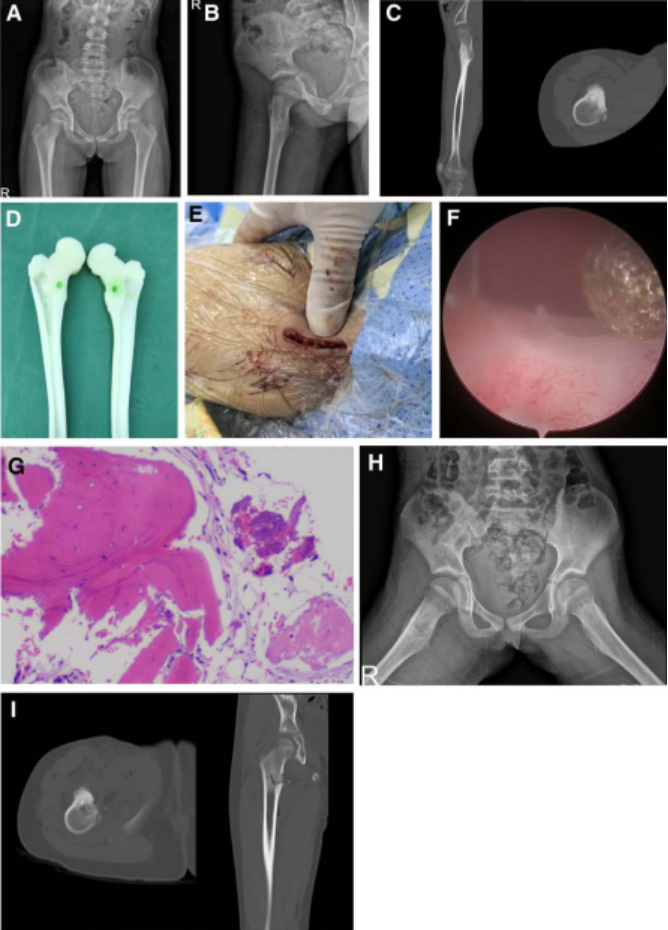

女性,49岁,检查发现发现左股骨近端占位性病变。患者无自觉症状,影像学显示左股骨近端椭圆形溶骨性病变,边界清晰,呈“磨玻璃样”改变,无皮质破坏或软组织侵犯。术前MRI提示囊性肿瘤样病变。初步诊断为良性骨肿瘤样病变。入院后广西医科大学第一附属医院脊柱骨病外科团队结合患者具体情况,制定个性化治疗方案。行AUNES辅助下肿瘤刮除+同种异体骨移植融合术。手术取左大腿近端外侧纵切口约1.5cm,透视引导下定位,逐步扩张通道,内窥镜下使用射频电极清理病灶周围组织,高速磨钻开骨窗,彻底刮除病灶后植入同种异体骨,术后病理提示骨纤维结构不良。术后第一天手术区轻度疼痛(VAS 3分),第三天出院。术后CT显示病灶腔完全被植骨填充,骨窗与肿瘤横径匹配良好。一个月随访时疼痛消失,切口愈合良好;三个月CT显示植骨融合进一步改善,无并发症发生。

图3 骨纤维结构不良患者术后影像